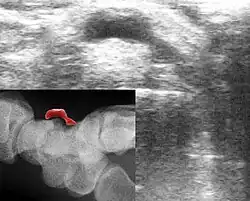

Diagnose

Die Diagnose eines Ganglions kann meist schon durch dessen Lokalisation oder Form gestellt werden. Die darüber liegende Haut ist verschiebbar, es besteht eine unveränderliche Verbindung zum Gelenk oder zur Sehnenscheide. Da aber auch andere Veränderungen ein ähnliches Bild bieten können, ist meist eine Sicherung der Diagnose nötig. Dies kann beispielsweise durch Nadelaspiration der Flüssigkeit, Ultraschall oder chirurgische Intervention geschehen. Im normalen Röntgenbild ist ein Ganglion nicht sichtbar. Die Röntgenaufnahme dient aber zum Ausschluss einer Knochenvorwölbung (Exostose). Besonders an der Basis des dritten Mittelhandknochens kann es auf dem Handrücken zu einer solchen Exostose kommen, die als Carpal boss mit einem Ganglion verwechselt werden kann.